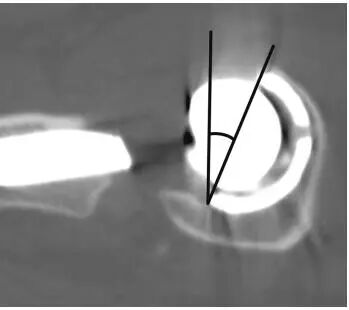

下图为CT测量前倾角(图8)